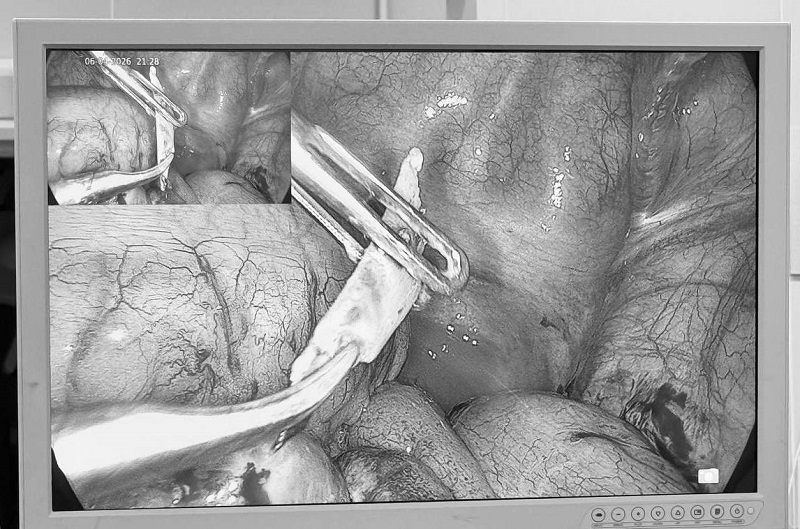

Dị vật là một mảnh xương nhọn dài khoảng 2,5 cm được lấy ra ngay khi nội soi

Trong quá trình mổ nội soi cấp cứu, các bác sĩ lấy ra dị vật là một mảnh xương nhọn dài khoảng 2,5 cm đã đâm thủng ruột hồi trang (ruột non) kèm ít dịch viêm xung quanh. Dị vật được lấy ra an toàn, tổn thương được xử trí triệt để, ổ bụng được làm sạch. Sau phẫu thuật, bệnh nhân hồi phục tốt, không còn sốt, vết mổ đau ít. Bệnh nhân được xuất viện sau 4 ngày theo dõi, điều trị nội trú tại khoa Ngoại, Bệnh viện Đa khoa MEDLATEC.